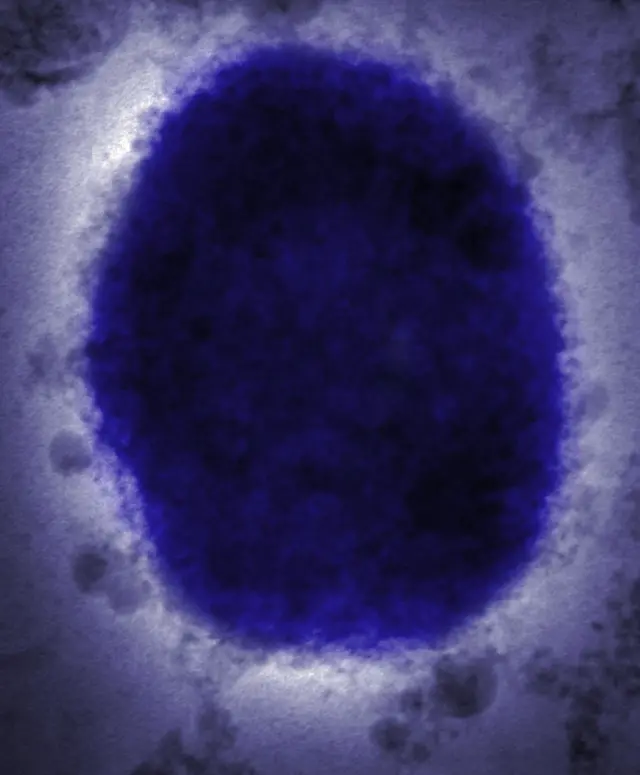

Sumber gambar, Science Photo Library

Penyakit cacar monyet disebabkan oleh virus cacar monyet, anggota genus Orthopoxvirus dalam famili Poxviridae, berdasarkan keterangan WHO.